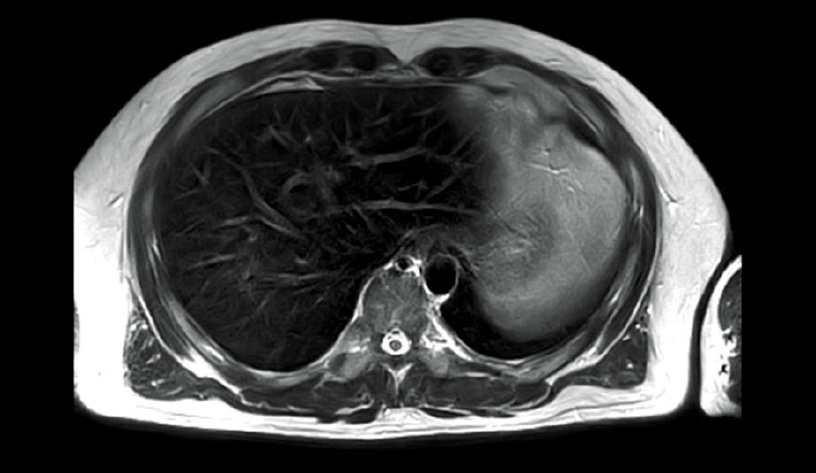

16 kanallı Alıcı Sistemi

Yüksek hızlı görüntüleme sırasında alıcı hassasiyetini ve stabilitesini artırmak için alıcı bobinlerinin sayısını ikiye katlama

Alıcı bobinlerinin elemanları, alıcı kanal sayısını 8’den 16’ya ikiye katlayacak şekilde küçültülmüştür. Bu, alıcı hassasiyetini artırmış, yüksek görüntü SN oranı elde etmiş ve bağımsız alıcının 8 kanallı bir sistem kullanılarak mümkün olmadığı, karın ve diğer bölgelerdeki çok kanallı alıcı bobinlerinden düşük gürültülü alıcı elde etmiştir. RAPID yüksek hızlı görüntüleme işlevi kullanıldığında, alıcı bobin elemanlarının sayısı ne kadar fazla olursa, genleşme bilgileri o kadar fazla elde edilebilir. Bu, stabil bir görüntüleme sağlar.